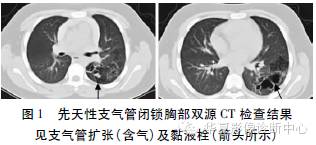

行胸部增强双源CT扫描示左肺上叶后段、下叶背段支气管扩张(含气)伴周围肺气肿改变,见图1。住院期间予头孢他啶抗感染,监测体温正常,咳嗽、咳痰症状明显好转。根据患者胸部双源CT表现确诊为CBA,建议外科手术治疗,家属拒绝,随访1年,病情稳定。

结合文献分析,本例胸部双源CT发现病灶临近支气管狭窄伴周围肺气肿形成,有典型的支气管截断伴黏液嵌塞、支气管扩张含气和同叶段周围肺组织气肿“三联征”表现,确诊为CBA。分析发病机制为在气管的发育过程中上皮曾过度增生,使管腔一度闭塞,而后过度增生的细胞退化并吸收,使管腔重建再通。